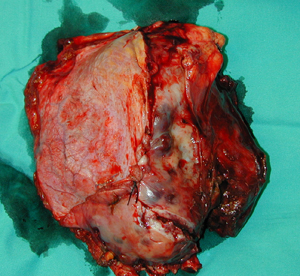

Περίπτωση Νο 3

Εικόνα 2

Φωτογραφία χειρουργικού παρασκευάσματος, ο όγκος διηθούσε μεγάλο τμήμα του διαφράγματος που αφαιρέθηκε en-block μετά των πλευρών και των μεσοπλευρίων μυών. Η ιστολογική εξέταση έδειξε ότι πρόκειται για μεταστατικό όγκο (αισθησιονευροβλάστωμα), πάνω από εικοσιπέντε χρόνια μετά από την αρχική θεραπεία του πρωτοπαθούς όγκου. Πρόκειται για σπανιότατο μεταστατικό όγκο του θωρακικού τοιχώματος.